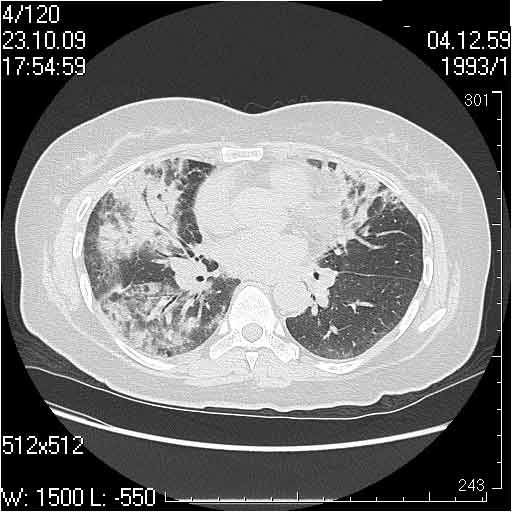

Случай №1

Женщина 50 лет.

Случай 1: изменения характерны для интерстициальной пневмонии (IIP/UIP idiopathic interstitial pneumonia/usual interstitial pneumonia); говорить о конкретной форме без открытой биопсии затруднительно.